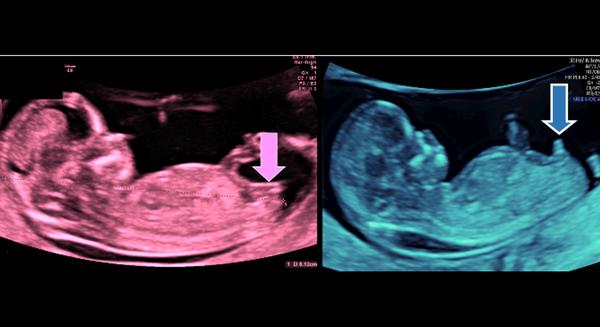

Aj mne povedali, že chlapec, ja sama som to videla 😀 a pravda samozrejme. Na tom 3D, keď sa dieťa ukáže, tak to je nádherne vidieť 🙂

Áno, hneď bolo pekne vidno, že je to chlapček tak ako na fotke vyššie. Ja som bola u MUDr Hatiara na prvom utz.